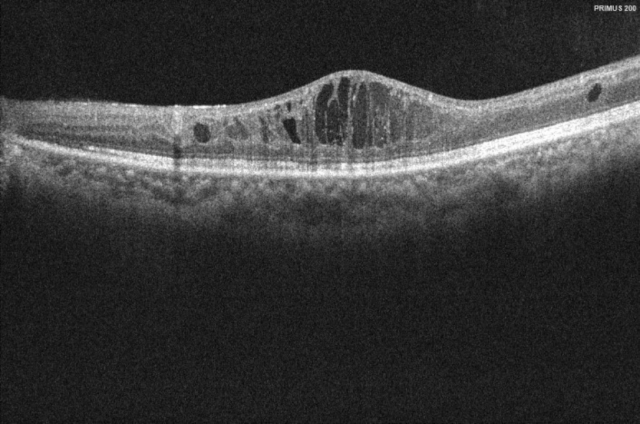

唐先生治疗前影像检查

唐先生接受“布西珠单抗”注射治疗后,复诊结果显示其黄斑囊样水肿消退,视网膜平复。

广州市一南沙医院眼科主任邱海江为唐先生进行了“布西珠单抗”注射治疗。一个月后,唐先生来医院复查,视力由原先的4.0成为现在的4.4,视力提升了4行。